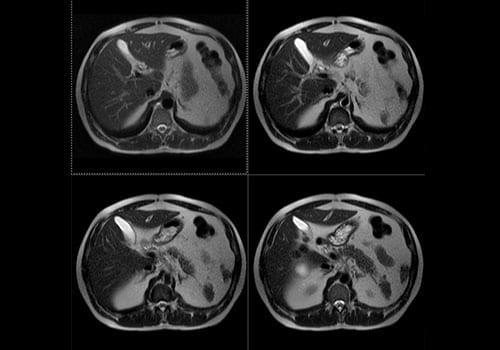

A mass in an organ can often not be accurately diagnosed. The body part with the contrast inside will appear lighter on the radiographic image than the surrounding tissue. The images below demonstrate the difference in the visibility of the.

A mass in an organ can often not be accurately diagnosed. Contrast is essential to fully say what an abnormality may be. Ct of the abdomen and pelvis is a special type of imaging performed with intravenous contrast material after the ingestion of oral barium.